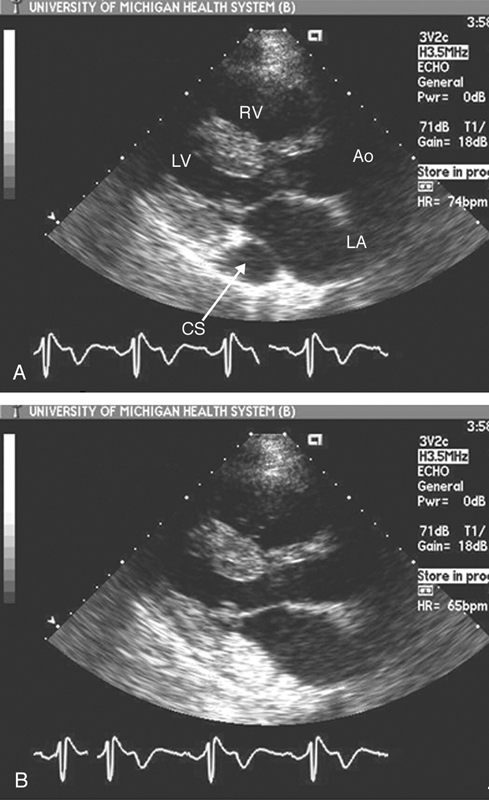

فحوصات تشخيصية لبعض امراض القلب والشرايين التاجية